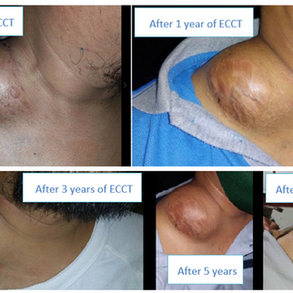

After the surgery, I continued traveling. I travelled for years. In 2024, I began to realize that the tumor had started growing again. I tried everything that was possible with alternative treatments, but I could see that it was growing very rapidly out of control. Over the following months, it grew rapidly. Imaging revealed a large, lobulated mass measuring approximately 44 × 50 mm. The skin over the breast became tense, discoloured, and painful, especially at night. An enlarged axillary lymph node raised further concern as well.

At some point, I understood that I needed more support. I contacted the ECCT team, and they explained to me how ECCT works. During the initial consultation, the team carefully reviewed my medical history, imaging, biopsy results, and symptoms. They encourage me to get proper biopsy and told me that it is likely recurrent of metastatic TNBC. The scan later on does confirm it’s TNBC involving my liver, bone, lung, and lymph nodes. The biopsy as well confirmed a highly aggressive recurrence. The tumour was again triple-negative, now with a Ki-67 of 90%, extensive necrosis, numerous atypical mitoses, and no PD-L1 expression, these features associated with fast growth and limited immunotherapy options.

When I first start for treatment, the tumour was very big. It was visible, and it was painful. My arm movement was restricted. I was very tired, and I had lost weight. Emotionally, it was very difficult for me.

After 2 months, the tumour started to change. It became softer, and it began to shrink. The pain reduced, and I could move my arm again. Slowly, my energy started to come back.

By December 2025, PET-CT imaging showed a clear and significant treatment response for my resolution of TNBC Ki-67 of 90%:

– The ulcerated breast tumour had become significantly smaller